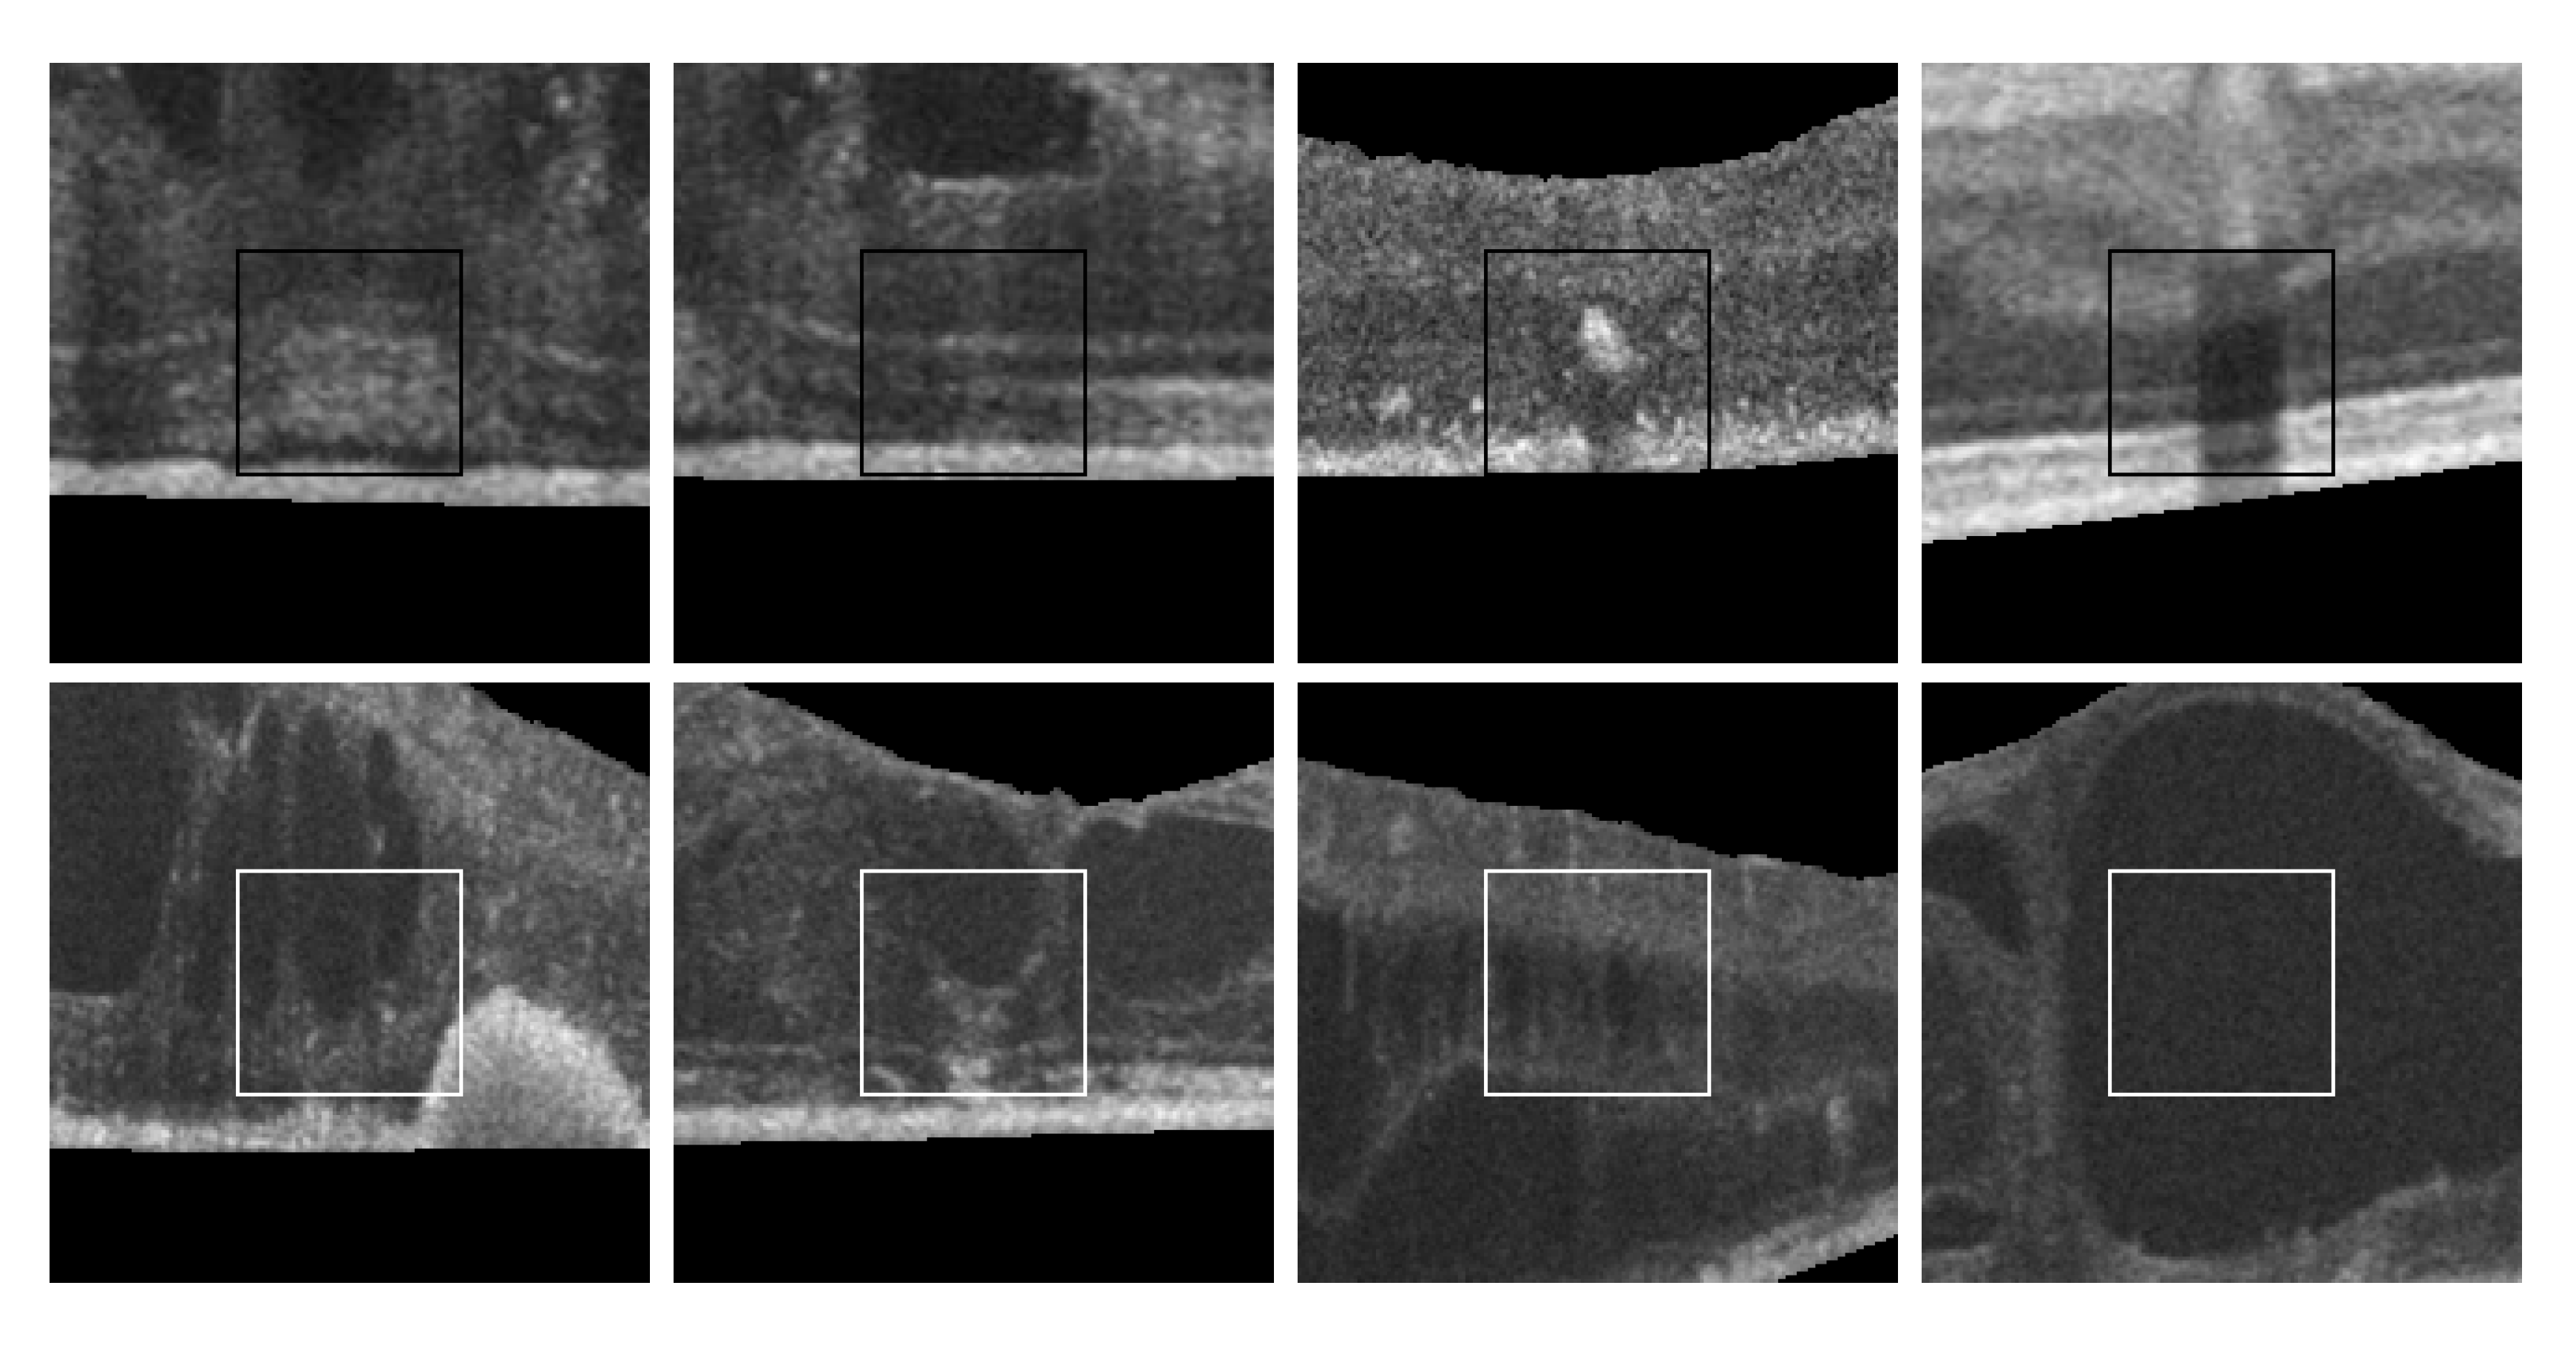

Finally, as shown in Figure 2, 2nd row, not all cysts have a precise border that can be segmented. Many times, these fluid regions can be clearly distinguished inside the retinal layers thanks to a significant contrast between the internal fluid and the surrounding neighboring tissues (as the examples of Figure 2, 1st row show). In these cases, a segmentational approach can produce acceptable results. However, many other times this process is not as simple as the previous ones. In other cases, cysts do not present enough contrast, being extremely difficult to accurately identify their entire contour (Figure 2, 2nd row, (a,b)) or they may appear in nearby groups that make extremely complicated the identification of their limits (Figure 2, 2nd row, (c,d)). In these cases, a regional classification with the identification of the cyst presence is more feasible and also clinically relevant for the medical analysis and diagnosis.

Figure 2. Examples with accumulations of intraretinal fluid with adequate definition for a segmentation (1st row) and counter-examples with blurred, merged, and obfuscated edges that are hard to segment precisely (2nd row). (a,b) Individual cystoid fluid bodies. (c,d) Groups of fluid accumulations.

Figure 14 includes some representative cystoid and non-cystoid regions that were selected from a test dataset and that were correctly classified. In the case of non-cystoid regions, the method is not only capable to identify the typical retinal layer patterns, but also other regions with a large diversity of irregularities. Thus, Figure 14, 1st row, shows some examples with the presence of pathological alterations or the projection of shadows that alter the intensity patterns. Generally, these cases were correctly handled by the method. Some representative cystoid regions are also presented in Figure 14, 2nd row, with examples of different levels of complexity including cysts with irregular contours, mixed with other pathological structures, nearby groups of cysts or fluid regions inside huge cysts, respectively, cases that the system was capable to handle.

Figure 14. Randomly selected samples from the test dataset labeled by experts that were correctly classified by the automatic system. 1st row, non-cystoid regions. 2nd row, cystoid regions.